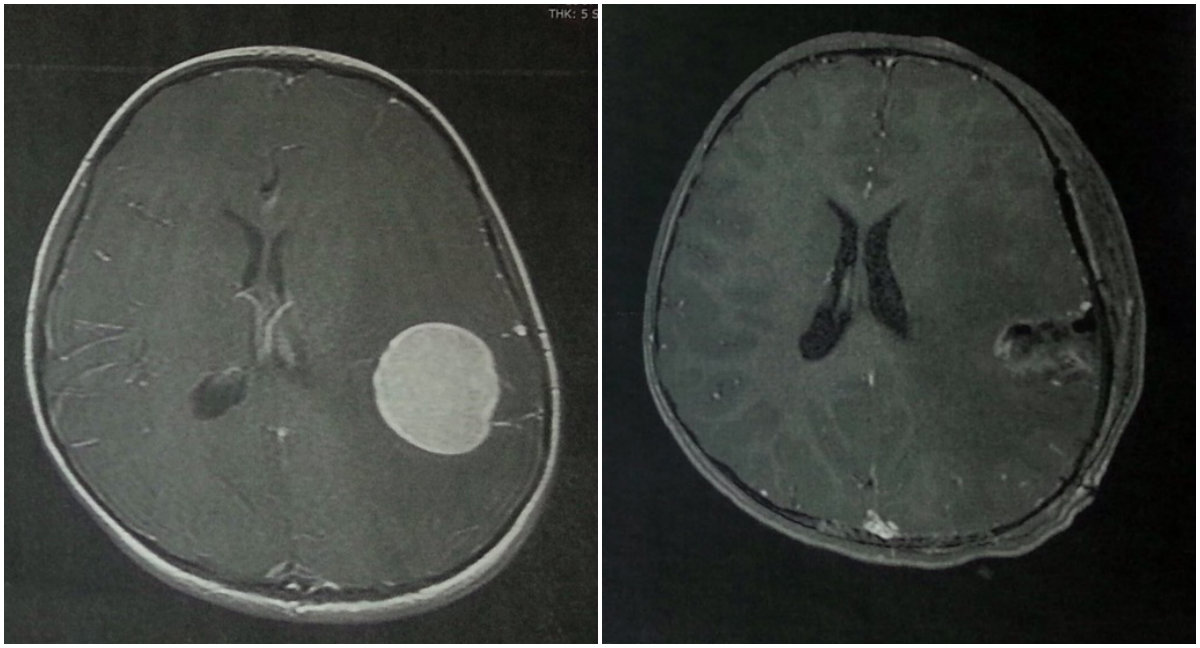

August 30, 2013. Worst day to date. Neurologist explains that (name withheld), age 5, has been losing her words and memory as a result of a primary brain tumor. Devastated. All light had gone from our lives and hearts.

INDIANAPOLIS — A father who sexually molested his 6-year-old daughter — as she endured chemotherapy and radiation to fight off a rare, cancerous brain tumor — will avoid years of prison time for his felonious acts.